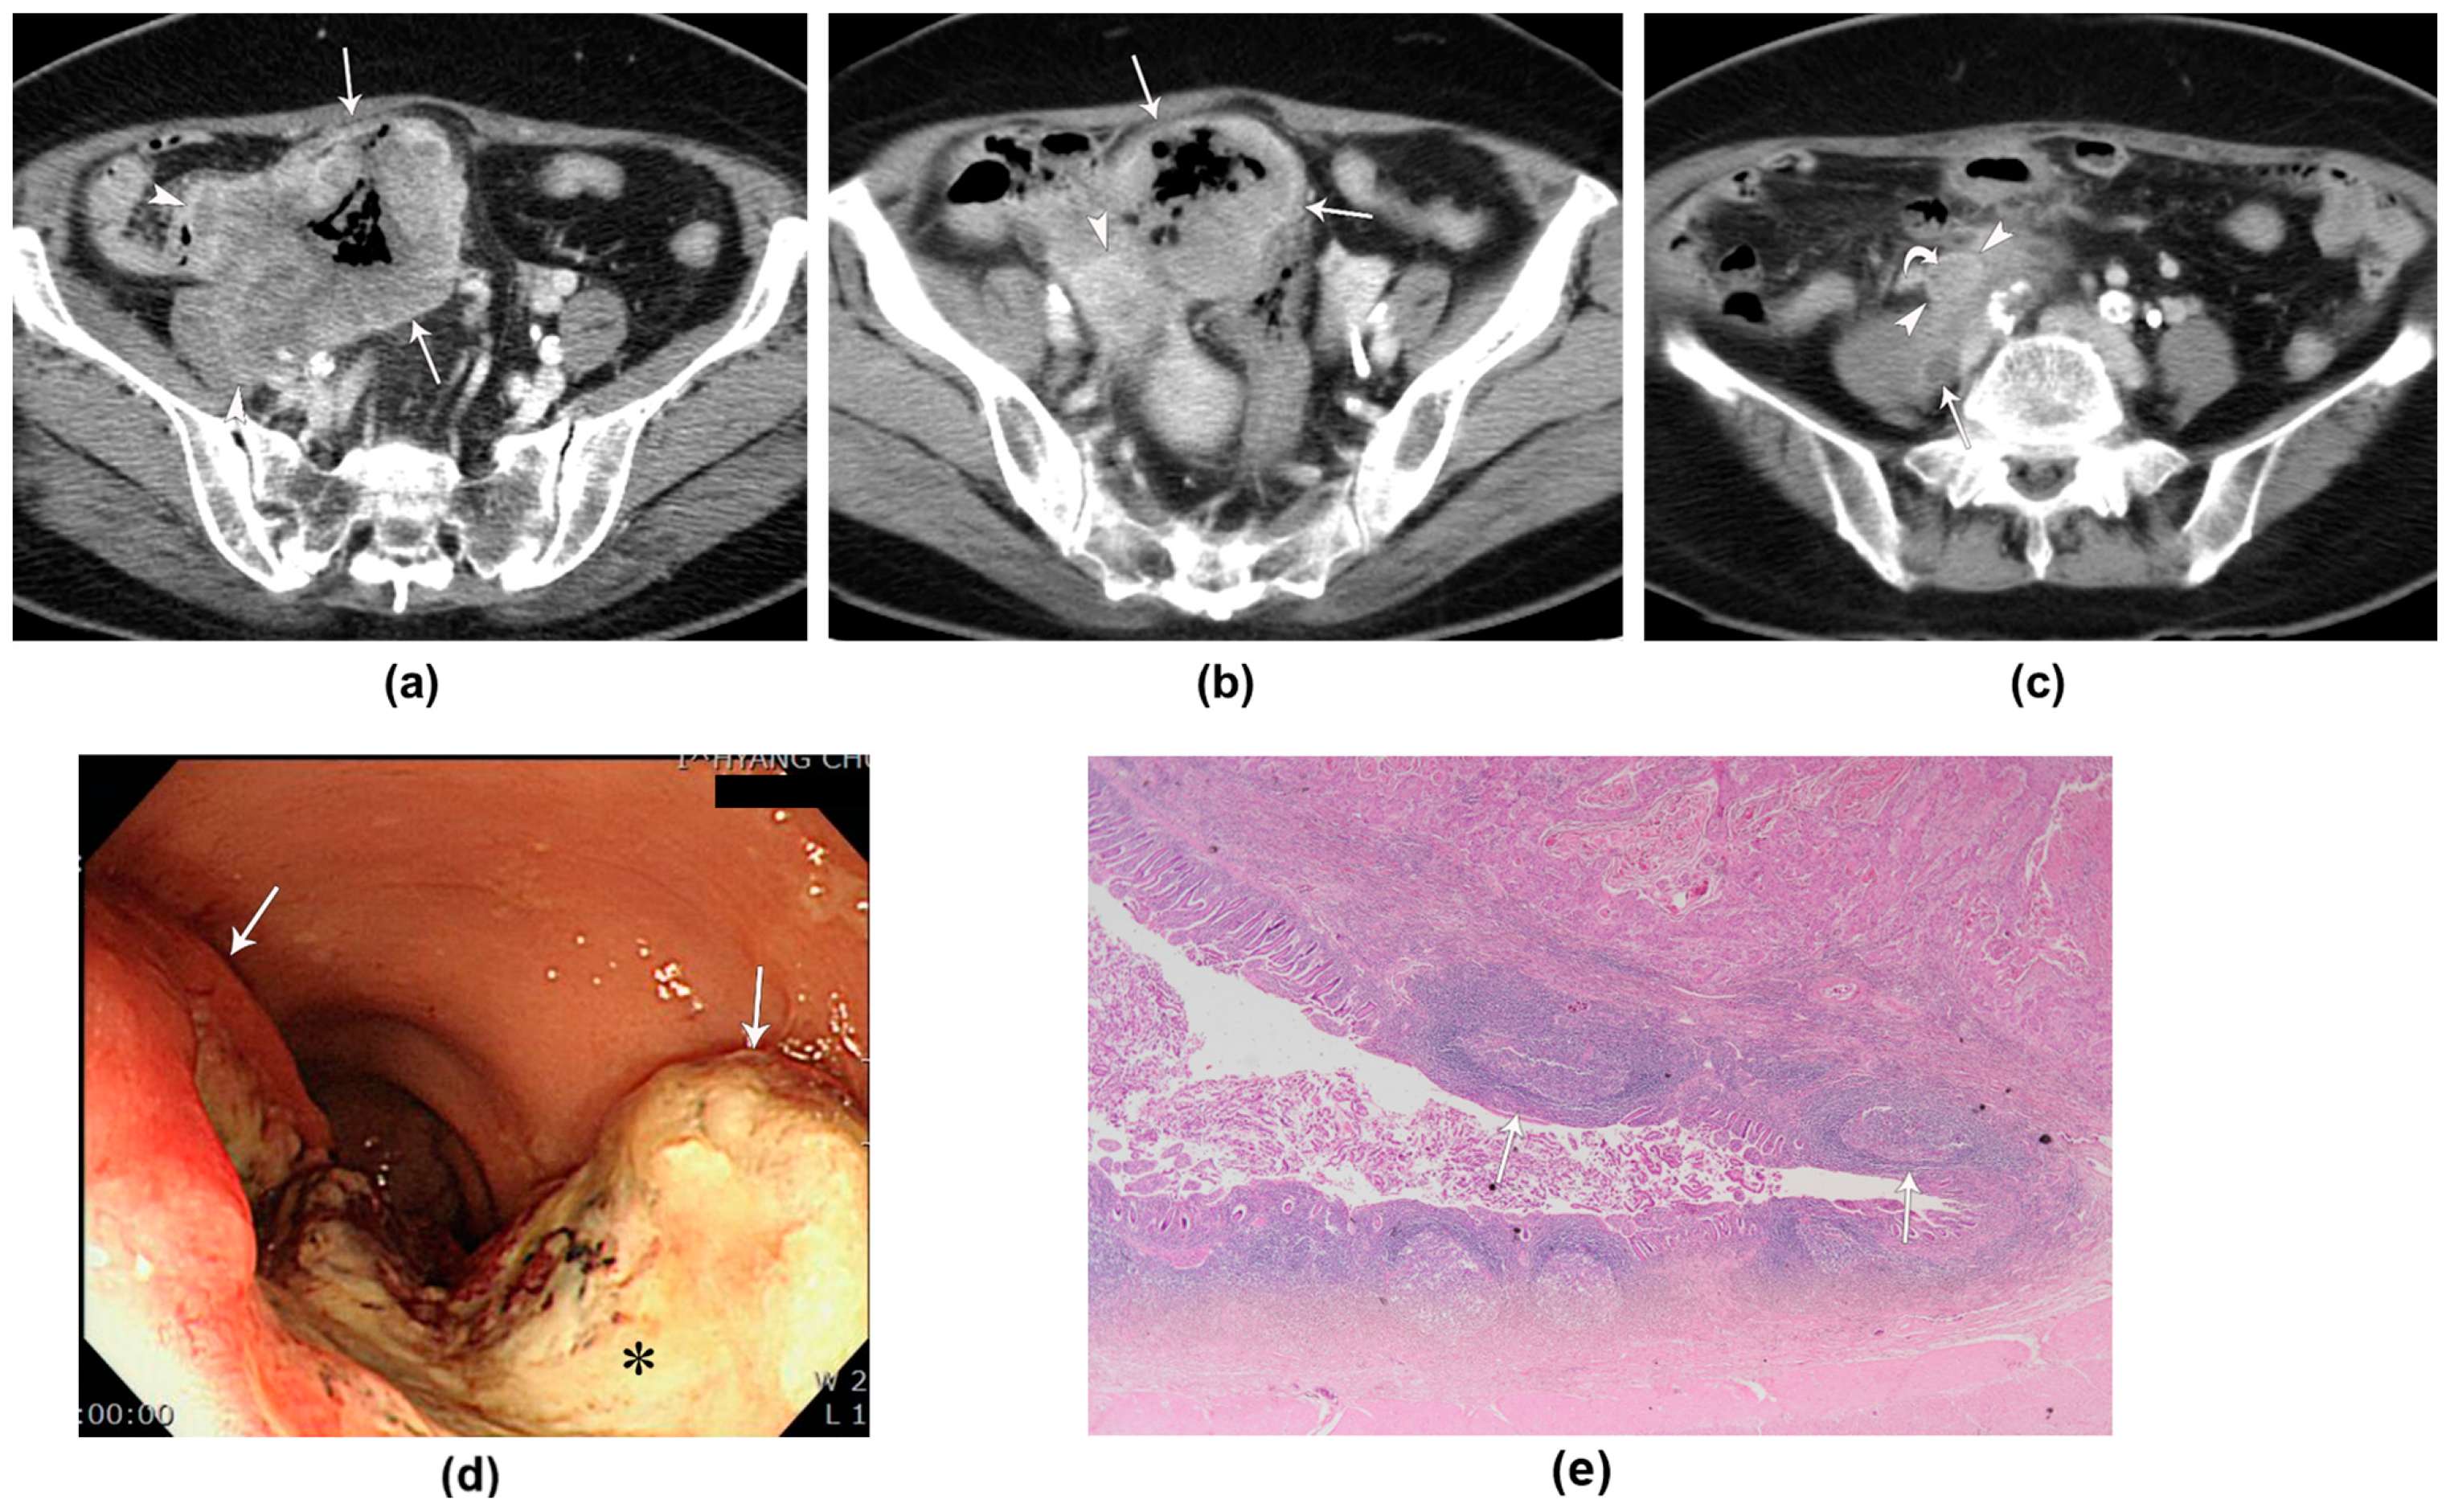

| 59/M | Hematochezia | CT, PET-CT | Rb | Circumferential wall thickening | 24 | Homogeneous | Moderate (1.22) | No | 10/21 | Yes | Levator ani muscle, prostate, urinary bladder | No |

| 67/F | Hematochezia | CT | Ra | Eccentric wall thickening | 14 | Homogeneous | Moderate (1.36) | Yes | 2/12 | Yes | No | No |

| 92/M | Hematochezia, constipation | CT | Rb | Bulky mass | 44 | Heterogeneous | Well (1.53) | Yes | 2/17 | Yes | Prostate | No |

| 54/F | Hematochezia | CT | Rb | Circumferential wall thickening | 19 | Homogeneous | Moderate (1.16) | Yes | 1/12 | Yes | No | No |